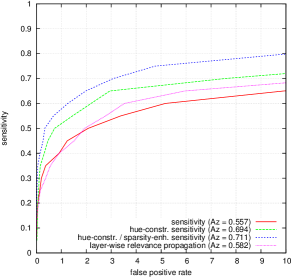

FROC curves are reported in Fig. 6 for ‘net B’; areas under the limited FROC curve for all three ConvNets are summarized in Table 3. It appears that the number of false alarms is rather large, particularly in the case of microaneurysm detection. The reason is that human experts primarily segmented the most obvious lesions, while screening algorithms need to focus on the most subtle lesions as well. In other words, many true lesions are counted as false alarms. Of course, this comment also applies to competing automatic solutions. To show the value of our detections, the proposed solution was compared in Fig. 7 to results reported in the literature, following the DiaretDB1 standardized procedure (see section 5.3.2). Most authors reported a single (sensitivity, specificity) pair: this is what we reported in Fig. 7. Some authors reported ROC curves; in that case, we also reported a single (sensitivity, specificity) pair: the one closest to the (sensitivity = 1, specificity = 1) coordinate. Note that all competing solutions (Kauppi et al., 2007; Yang et al., 2013; Franklin and Rajan, 2014; Kumar et al., 2014; Bharali et al., 2015; Mane et al., 2015; Dai et al., 2016) are trained at the lesion level, while ours is trained (in Kaggle-train) at the image level.

Three ConvNets were trained to detect referable DR in the Kaggle-train dataset, using the proposed heatmap optimization procedure. Then, we evaluated how well those ConvNets could detect lesions in the DiaretDB1 dataset, without retraining them. For lesion detection at the image level, they outperformed previous algorithms, which were explicitly trained to detect the target lesions, with pixel-level supervision (see Fig. 7). This superiority was observed for all lesions or groups of lesions, with the exception of ‘red lesions’. Experiments were also performed at the lesion level: for all lesion types, the proposed algorithm was found to outperform recent heatmap generation algorithms (see Table 3). As illustrated in two examples (see Fig. 9 and 10), the produced heatmaps are of very good quality. In particular, the false alarms detected on the vessels, in the vicinity of true lesions in the unoptimized heatmaps ( maps), are strongly reduced with sparsity maximization (, , ). These experiments validate the relevance of image-level supervision for lesion detectors, but stress the need to optimize the heatmaps, as proposed in this paper. Note that detection performance is not affected much by image quality: very good detections are produced in the blurry image obtained with a low-cost, handheld retinograph (see Fig. 10). This is a very important feature, which opens the way to automated mobile screening. However, it can be observed that the ‘AlexNet’ architecture, which achieves moderate DR detection results, also achieves poor detection results at the lesion level, even after heatmap optimization (see Table 3): to ensure good detection performance at the lesion level, the proposed optimization framework should be applied to ConvNet architectures that achieve good image-level performance.